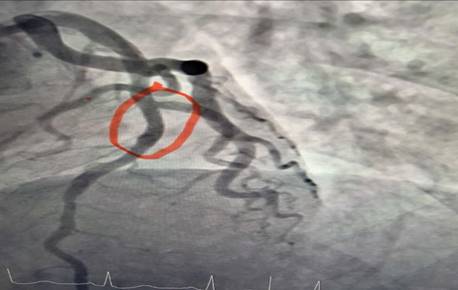

Hình ảnh động mạch vành tái thông sau can thiệp

Ê-kíp bác sĩ khoa Nội tim mạch đã tiến hành chụp động mạch vành kết quả cho thấy: nhánh động mạch thủ phạm gây Nhồi máu cơ tim cấp là đoạn 1 động mạch liên thất trước hẹp 95%. Bệnh nhân đã được can thiệp nong và đặt Stent động mạch vành giúp tái thông dòng máu nuôi tim, hạn chế tối đa tổn thương cơ tim và các biến chứng nguy hiểm. Sau can thiệp mạch vành tái thông tốt, tình trạng người bệnh ổn định, các triệu chứng đau ngực giảm rõ rệt và tiếp tục được theo dõi, điều trị theo phác đồ chuyên môn.